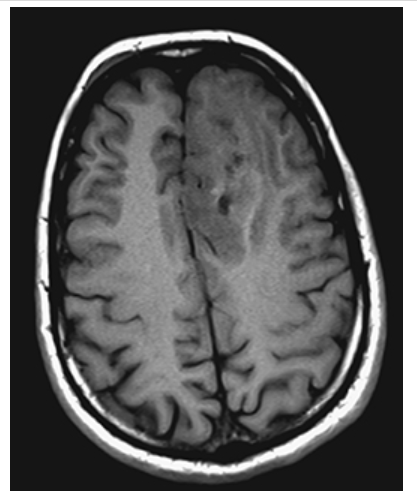

What is A

Arteriovenous Malformation. Axial T1W pre- and postcontrast

What is B

Arteriovenous Malformation. Axial T1W pre- enhanced images show a left frontal lobe mass with surrounding edema, minimal peripheral enhancement, and “worm”-like flow voids.